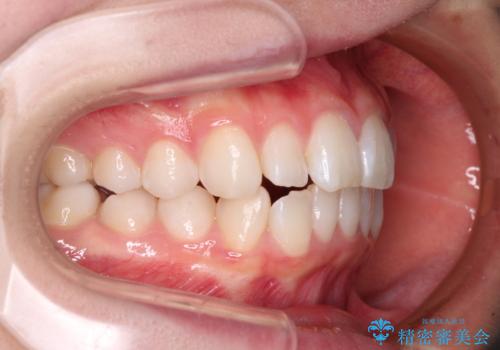

- 前歯の出っ歯と口元の閉じにくさを気にして来院された患者様です。

口元を積極的に引っ込めるために、上下左右の小臼歯4本を抜歯することとしました。

4本の歯を抜歯したことで、飛び出していた口元が引っ込み、横顔が大きく改善されました。